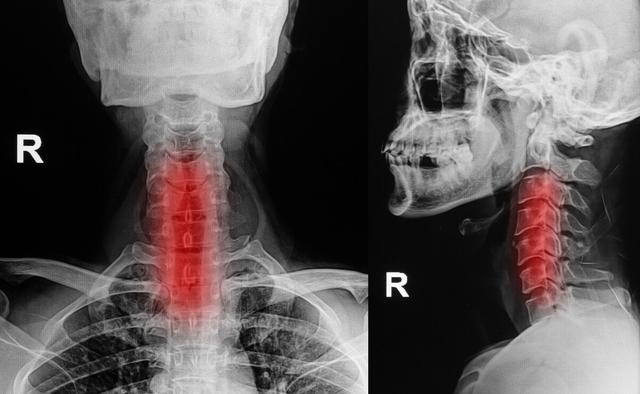

1. spondylose cervicale

Pour certains types de patients atteints de spondylose cervicale, l'engourdissement des extrémités des doigts est l'un des symptômes possibles, mais les patients atteints de spondylose cervicale, outre l'engourdissement des doigts, peuvent également être accompagnés d'autres symptômes, tels qu'une faiblesse des membres supérieurs et inférieurs, des douleurs dans la nuque, des difficultés à marcher, des bourdonnements d'oreille, une lourdeur dans la nuque, des vertiges, des nausées et d'autres symptômes. Il n'est pas difficile de diagnostiquer la spondylose cervicale, il suffit de se rendre dans un service d'orthopédie pour effectuer des examens radiologiques et obtenir un diagnostic clair.

IV. spondylose cervicale Spondylose cervicale

Si la compression de la spondylose cervicale causée par l'engourdissement de la main droite, la spondylose cervicale causée par les symptômes de compression nerveuse, il est recommandé d'effectuer des massages de physiothérapie, et il est interdit de s'engager dans de longues heures de travail devant l'ordinateur, la conduite, etc, et il y a une situation qui est d'aller à l'hôpital pour effectuer un test de pression artérielle il n'y a pas d'hypertension artérielle, il n'y a pas de maux de tête et de vertiges.

La spondylose cervicale, les ostéophytes, les hernies discales, etc., sont susceptibles de bloquer les racines nerveuses qui se ramifient à partir de la moelle épinière, et si elles sont bloquées, un engourdissement des mains peut également se produire, et l'engourdissement des mains se manifeste de la même manière que le syndrome du défilé thoracique. Mais cette affection causée par l'engourdissement des mains s'accompagne d'une gêne, d'une raideur, d'une douleur et de restrictions d'activité plus évidentes au niveau de la colonne vertébrale cervicale.

② La spondylose cervicale fait également partie des maladies courantes qui provoquent un engourdissement des doigts.

Lorsque les patients ont des problèmes de colonne vertébrale, la compression des nerfs du plexus brachial entraîne un engourdissement des mains et des douleurs dans les mains, ce qui provoque une insuffisance de l'irrigation sanguine du cerveau, des vertiges et des nausées. L'engourdissement des mains causé par la spondylose cervicale se manifeste principalement par un engourdissement unilatéral, par exemple du pouce et de l'index, ou de l'auriculaire et de l'annulaire, et le patient éprouve une inflexibilité des doigts, comme des difficultés à attacher des boutons et à tenir des baguettes. La manifestation de la spondylose cervicale, outre l'engourdissement des doigts, s'accompagne de douleurs musculaires au niveau du cou et des épaules, de douleurs irradiant dans les membres supérieurs et d'autres symptômes. Par conséquent, lorsque les symptômes d'engourdissement unilatéral des mains apparaissent, il convient de se demander s'il s'agit d'une spondylose cervicale.

5. spondylose cervicale

La spondylose cervicale est le principal facteur conduisant à l'engourdissement des doigts, en raison de facteurs à long terme conduisant à la protrusion des vertèbres cervicales, ce qui comprime les nerfs et les vaisseaux sanguins des deux côtés. La principale cause de l'engourdissement des doigts est la compression du nerf du plexus brachial ou du nerf cervical, de sorte que la lésion du nerf du plexus brachial ou du nerf du plexus cervical ainsi que la lésion des nerfs des membres supérieurs peuvent provoquer un engourdissement des doigts.